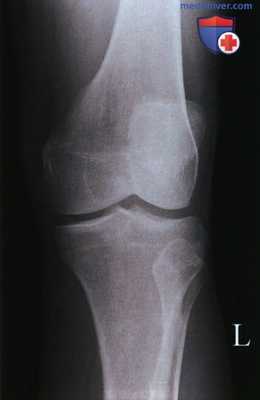

Передне-задняя рентгенограмма коленного сустава: характерная картина, при которой головка малоберцовой кости занимает в некоторой степени задненаружное положение относительно латерального мыщелка большеберцовой кости. Боковая рентгенограмма: межмыщелковая вырезка, которая определяется по линии Блуменсаата (Blumensaat). Медиальный мыщелок бедренной кости несколько крупнее латерального. Латеральный мыщелок бедренной кости может быть также идентифицирован по наличию борозды латерального мыщелка в его передней нагружаемой области. Боковую рентгенограмму получают обычно в положении небольшого сгибания. Обратите внимание на задний наклон поверхности большеберцовой кости, который должен составлять примерно 10°. Аксиальная рентгенограмма: коленный сустав в положении сгибания 20° (состояние максимального подвывиха надколенника). Обратите внимание, что латеральная фасетка надколенника вытянута и имеет менее острый угол, чем медиальная. Описано множество фасеток надколенника, однако медиальная и латеральная имеют наибольшее клиническое значение.

о Стандартные проекции включают в себя передне-задние проекции в положении стоя, боковые с небольшим сгибанием и аксиальные проекции надколенника при сгибании 20°

• Надмыщелки бедренной кости видны в профиль, мыщелки бедренной кости симметричны

• Межмыщелковое возвышение находится в центре межмыщелковой ямки

• Большеберцовая кость перекрывает половину головки малоберцовой кости (рис. 6-10)

• Суставная щель коленного сустава открыта

• Передний и задний края большеберцовой кости совмещены

• Головка малоберцовой кости визуализируется на 1,25 см дистальнее верхней суставной поверхности большеберцовой кости (рис. 14 и 18)